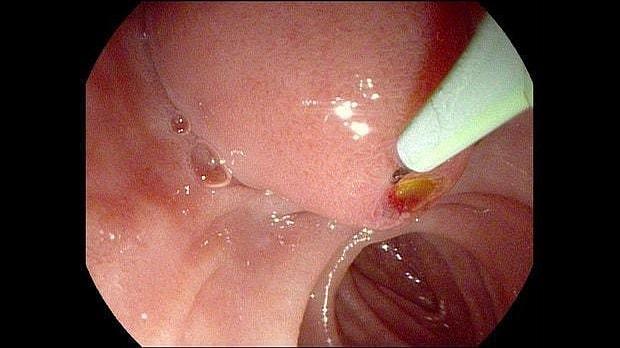

Здравствуйте. Пациентка, 32 года. Поступила на хирургическое отделение с диагнозом ЖКБ: холедохолитиаз. По данным МРТ: ЖКБ, множественные мелкие конкременты холедоха. При дуоденоскопии выявлено наличие вклиненного конкремента большого дуоденального сосочка. Выполнена прекатсфинктеротомия, получено 3 конкремента, диаметром около 0.4-0.5 см. Далее канюляция холедоха проволочным папиллотомом, выявлены многочисленные конкременты холедоха. Выполнена литоэкстракция ревизионным баллоном (на последнем фото окклюзионная холангиография - в просвете холедоха не конкременты, а пузырьки воздуха)).